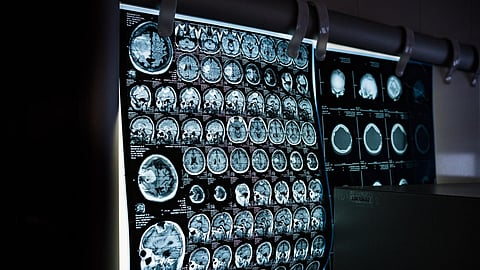

In the study, Li and colleagues performed just such a mapping. They first gathered a set of 1,037 high-quality magnetic resonance imaging (MRI) scans of infants in the third-trimester-to-two-year age interval. The scans came from two other research projects, the UNC/UMN Baby Connectome Project (BCP) and the Developing Human Connectome Project. The team analyzed the scan data using state-of-the-art, computer-based image-processing methods, essentially dividing the cortical surface into a virtual mesh containing thousands of tiny circular areas, and calculating the surface expansion rate for each of these areas.